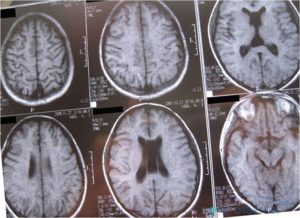

Основные методы инструментальной диагностики – исследование в формате МРТ или КТ. Нейровизуализация позволяет детально рассмотреть кисту, определить ее диаметр, морфологическое строение, точную локализацию, выявить характер влияния на окружающие ткани. Другие способы диагностики:

- МРТ или КТ позволяют локализовать размер и характер образований;

Для постановки точного диагноза в медицинских учреждениях используют два основных метода диагностики – компьютерная или магнитно-резонансная томография мозга. Любой из этих способов выявляет место расположения, размеры новообразования, а также общее число очагов. МРТ считается более показательной, поскольку точно определяет наличие мелких кистозно-глиозных поражений.